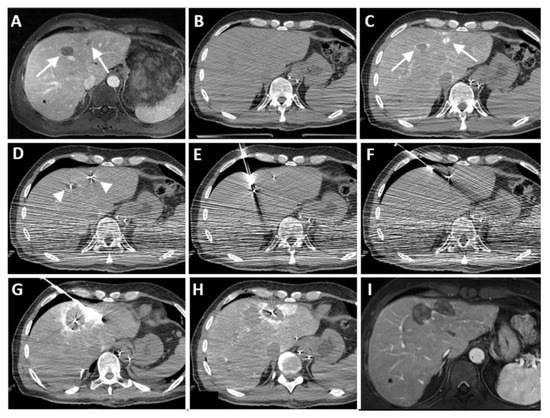

| Case No. | Tumor Size (mm) | Catheter Tip Position | Amount and Type of Contrast per Injection | Ablation Device | Institute |

|---|---|---|---|---|---|

| 1 | 20 mm | Common hepatic artery | 15–20 mL Visipaque™ | Emprint™ Microwave Ablation System, Medtronic-Covidien, Boulder, CO, USA | MD Anderson, Houston, TX, USA |

| 2 | 20 and 7 mm | Common hepatic artery | 4 mL Xenetix 300® | Cool-tip™ RFA Ablation Aystem, Medtronic-Covidien, Boulder, CO, USA | Gustave Roussy, Villejuif, France |

| 3 | 12 mm | Left-sided hepatic artery | Not specified | Cool-tip™ RFA Ablation System | Gustave Roussy |

| 4 | 9 mm | Common hepatic artery | 10 mL Xenetix 300® | Emprint™ Microwave Ablation System | Amsterdam UMC, Amsterdam, The Netherlands |

| 5 | 15 mm | Coeliac trunk | 20 mL Xenetix 300® | Emprint™ Microwave Ablation System | Amsterdam UMC |

| 6 | Not applicable | Common hepatic artery | 20 mL Xenetix 300® | Emprint™ Microwave Ablation System | Amsterdam UMC |

| 7 | Confluent | Common hepatic artery | 10 mL Xenetix 300® | NanoKnife system under ECG-gating; AccuSync model 72, AngioDynamics, Latham, NY, USA | Amsterdam UMC |

| 8 | 15 mm | Common hepatic artery | 15–20 mL Visipaque™ | Emprint™ Microwave Ablation System | MD Anderson |